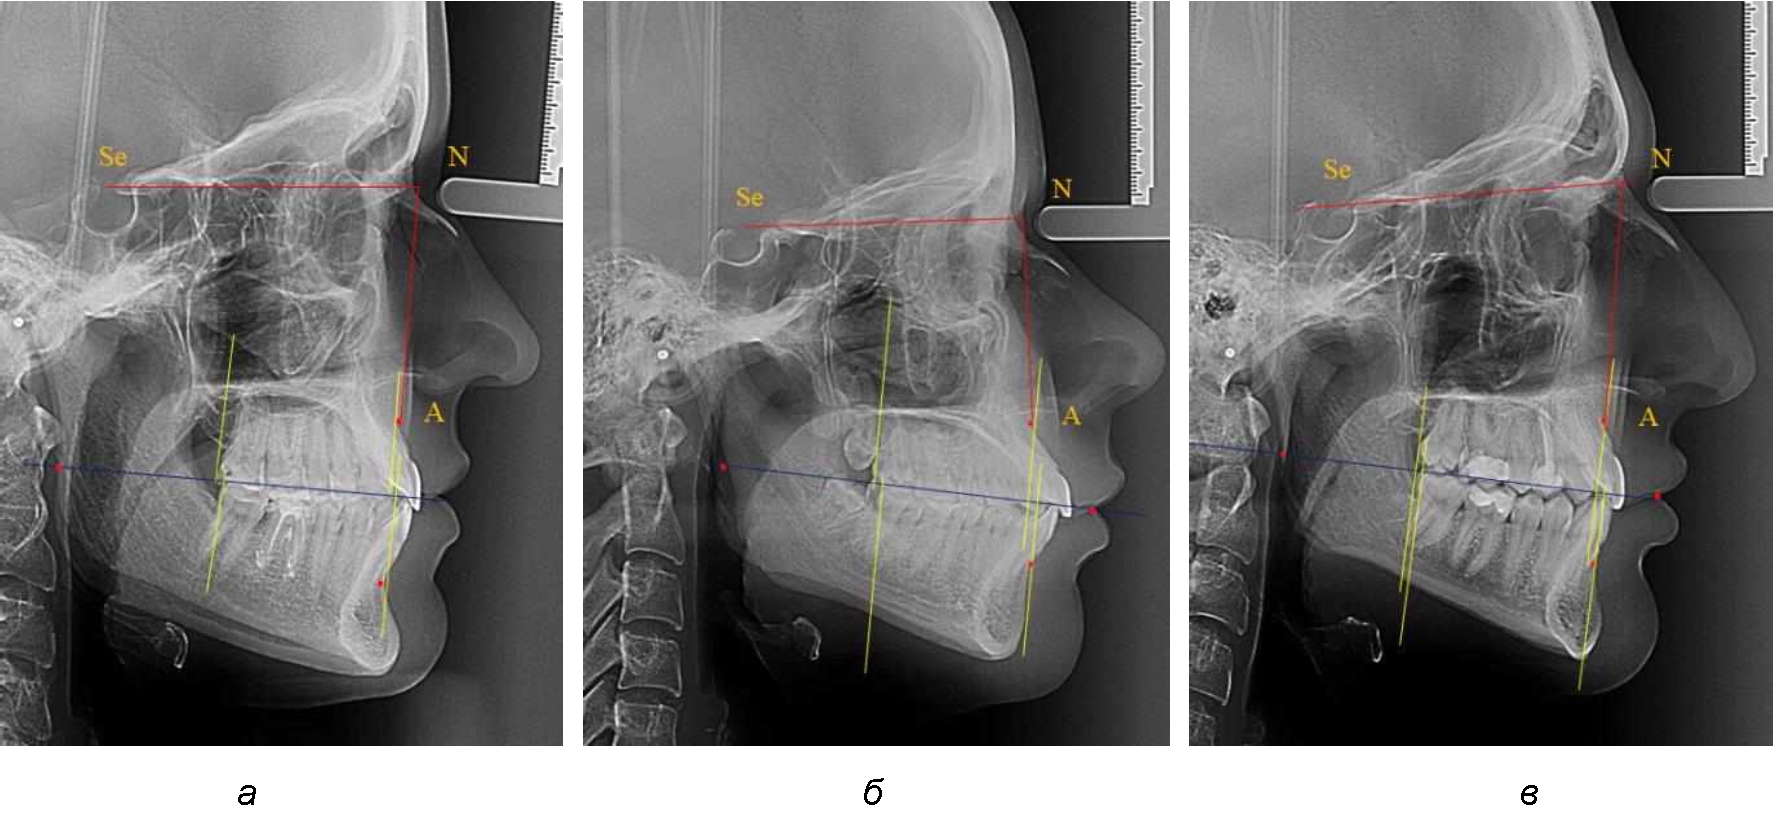

На рентгенограммах устанавливали точки Downs. На верхней челюсти субспинальная точка A(SS) располагалась в наиболее вогнутой точке альвеолярного отростка по переднему его краю. На нижней челюсти супраментальная точка B(SM) соответствовала месту наибольшей вогнутости переднего края альвеолярной части. Окклюзионную линию проводили через контактную точку резцов (vРOcP) и дистальную точку окклюзии второго нижнего моляра (hРOcP). Место пересечения окклюзионной линии с дистальным краем ветви нижней челюсти (ramus mandibule) обозначали как «rmРOcP». Перпендикулярно к окклюзионной плоскости проводили линии из точек «А(SS)» и «В(SМ)», что определяло их проекцию на окклюзионную линию. Аналогично отмечали положения дистальных окклюзионных точек верхней и нижней челюсти (рис. 1).

Рис. 1. Положение основных точек (а) и линейных ориентиров (б) для анализа положения и размеров челюстей

Альвеолярно-дентальный размер верхней челюсти и нижней челюсти оценивали по окклюзионной линии между вертикалями, ограничивающими исследуемые челюсти. Положение верхней челюсти оценивали по величине размера «rmOcP-А», а нижней челюсти по расстоянию «rmOcP-В». Линия смыкания губ обозначалась как точка «sto», вблизи которой проходила окклюзионная линия. Данный ориентир позволял провести окклюзионную плоскость при аномалиях положения резцов в вертикальном направлении, когда была сложность определения резцовой окклюзионной точки (vРOcP).

Аналогичное расстояние было отмечено и при расположении дистальных окклюзионных точек верхней и нижней челюсти (рис. 2).

Рис. 2. Положение апикальных точек и челюстей при нормопозиции (а), антепозиции (б) и ретропозиции (в) верхней челюсти